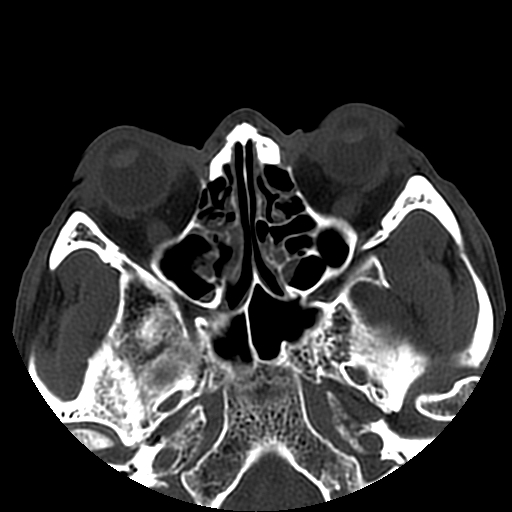

以下是引用liaoqiang在2008-7-16 21:15:00的发言:[br]右侧鼻骨骨折

以下是引用zxd95在2008-7-16 21:39:00的发言:[br]右侧上颌骨额突骨折。[br][br][br][br]